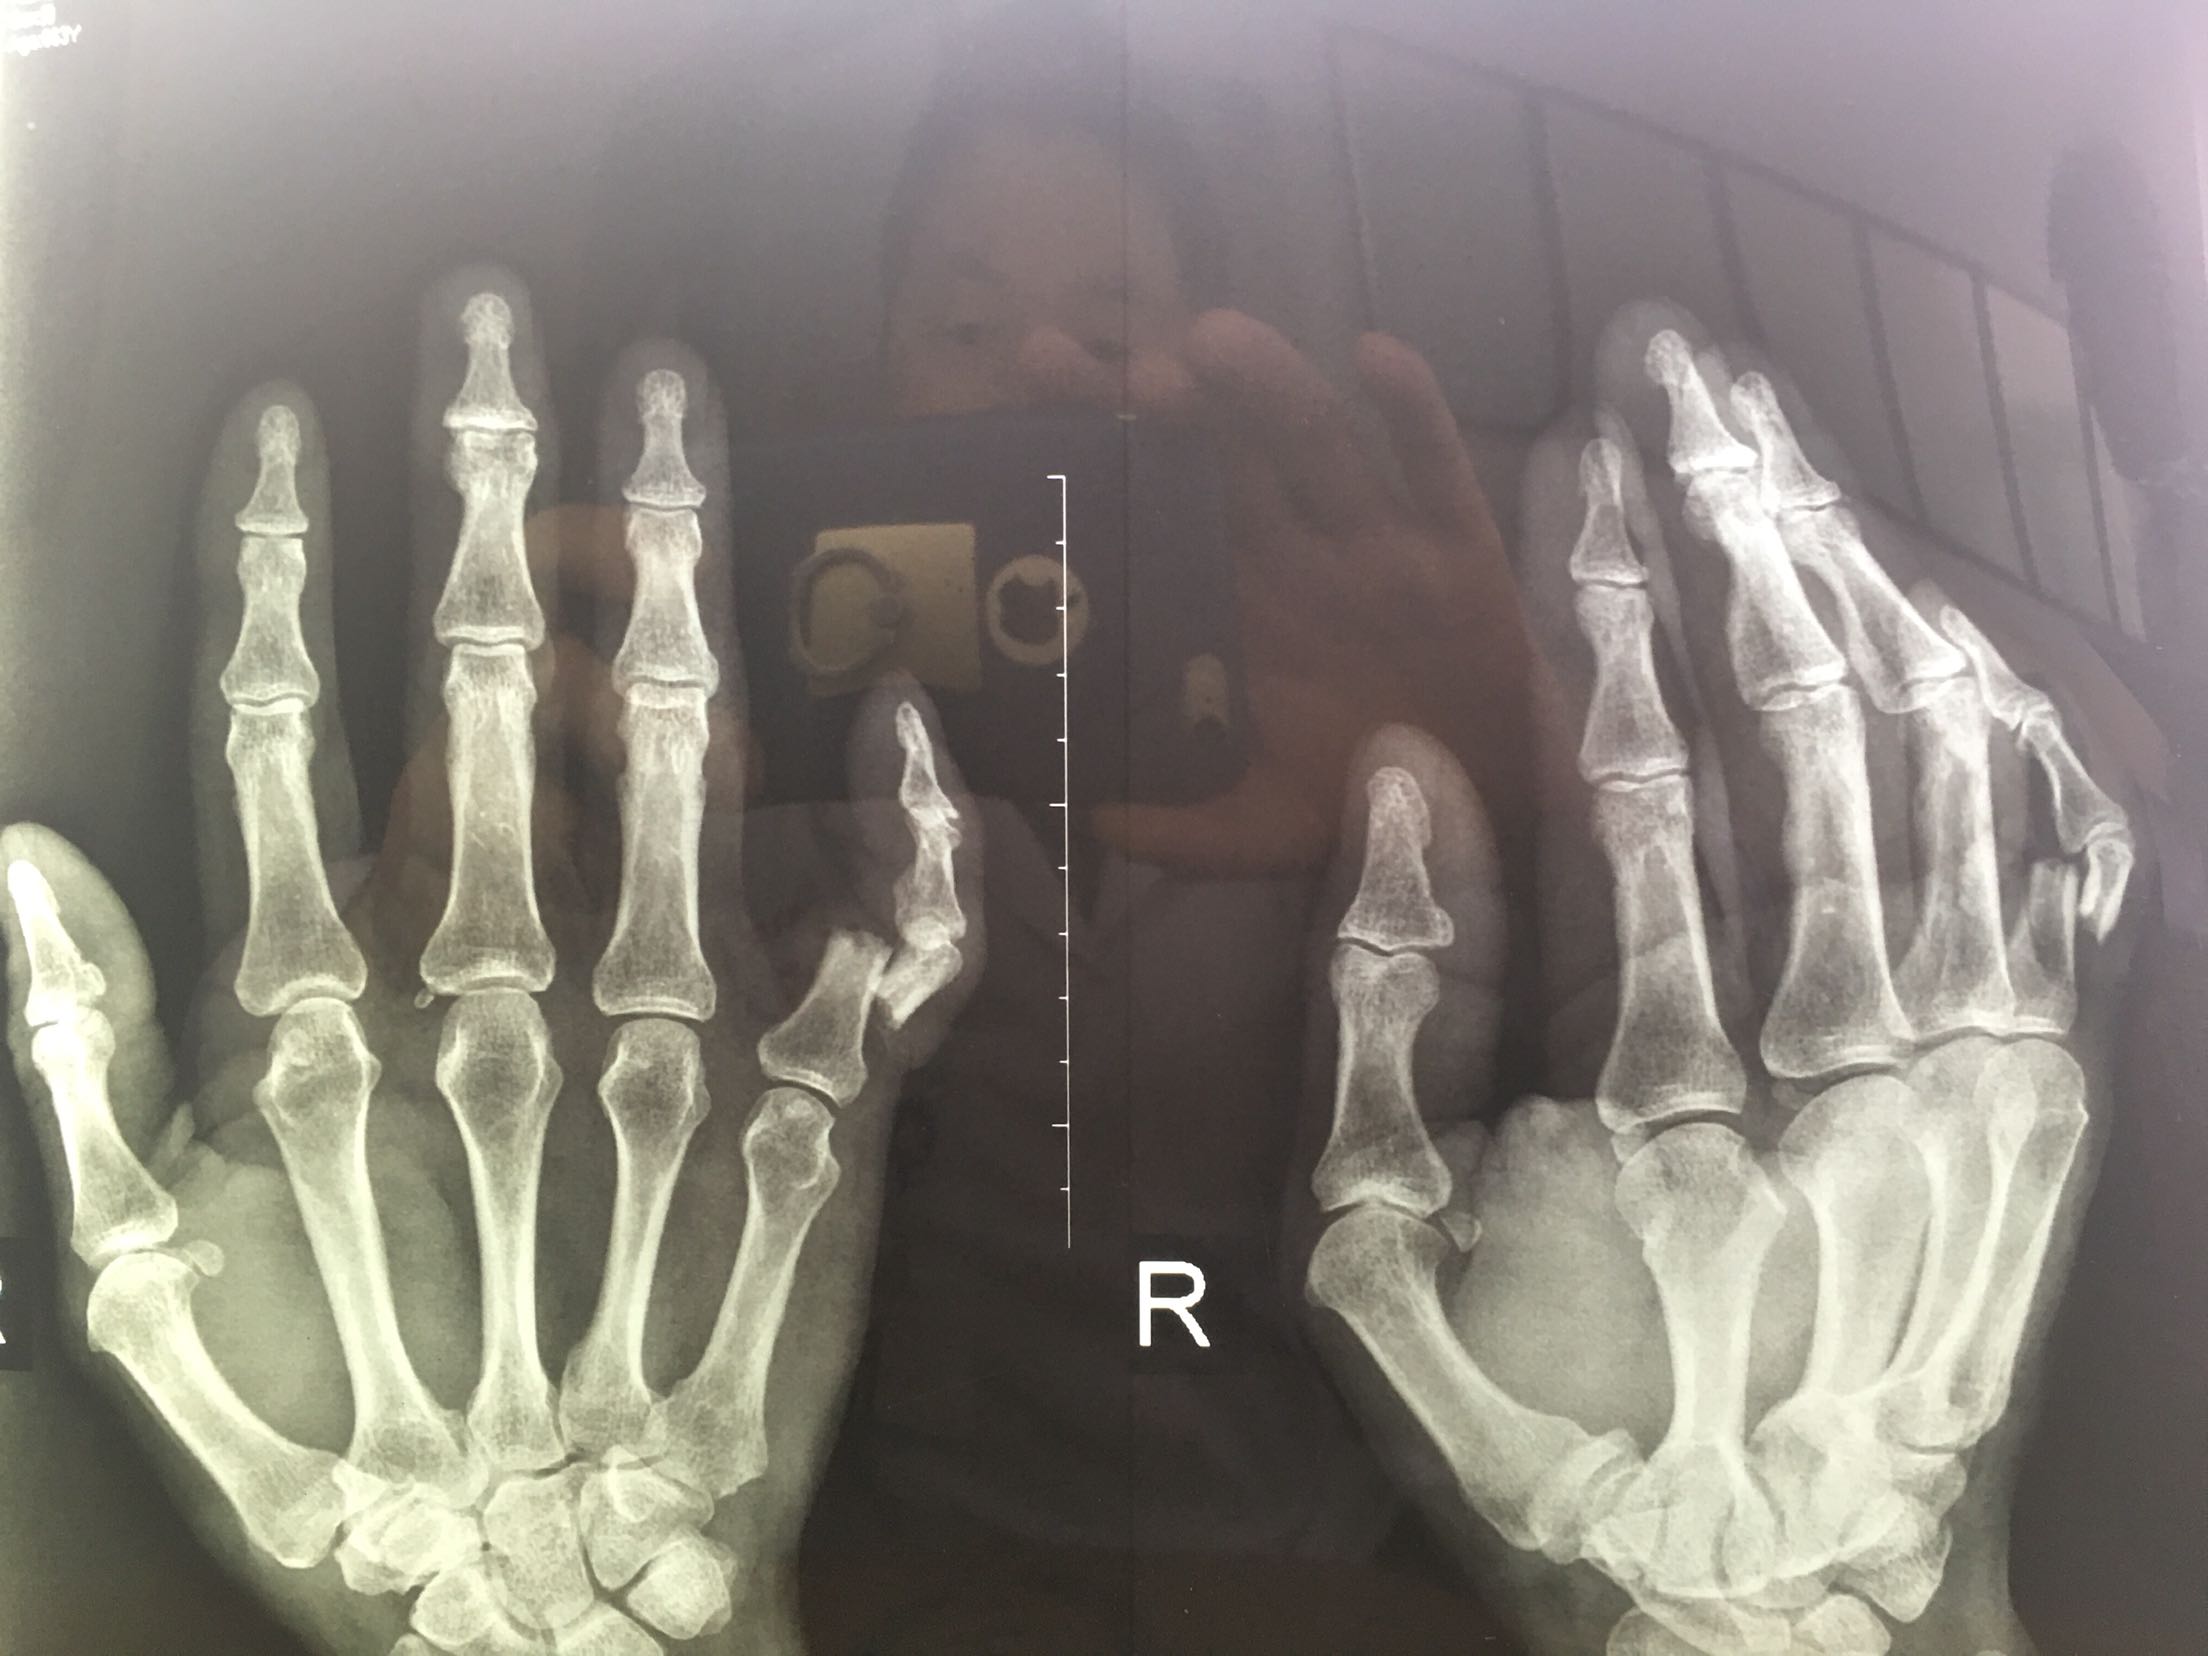

右小指开放性骨折

患者,男,63岁,砸伤后右手小指疼痛,出血,畸形30分钟。

右小指近节端尺侧可见一近弧形伤口,长约三厘米,软组织挫伤严重,活动性出血,末节感觉麻木,指腹欠饱满,张力低,皮色稍苍白,皮温低,活动障碍。